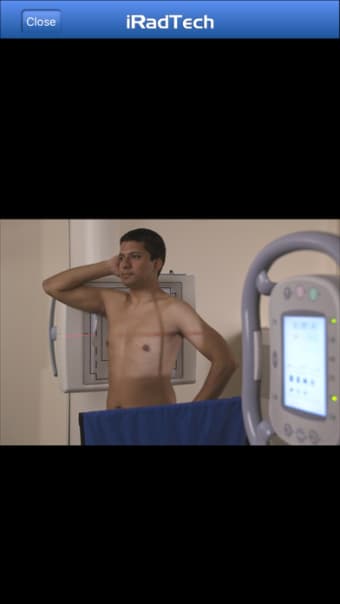

Un'applicazione versione completa per iPhone, di Ballinger e Bruckner LLP.

IRadTechè un programma completo per iPhone, che fa parte della categoria 'Medicina'.

IRadTech funziona su iOS 12.1.2 e versioni successive. La versione attuale dell'app è 4.0.1 e puoi eseguirla solo in inglese.